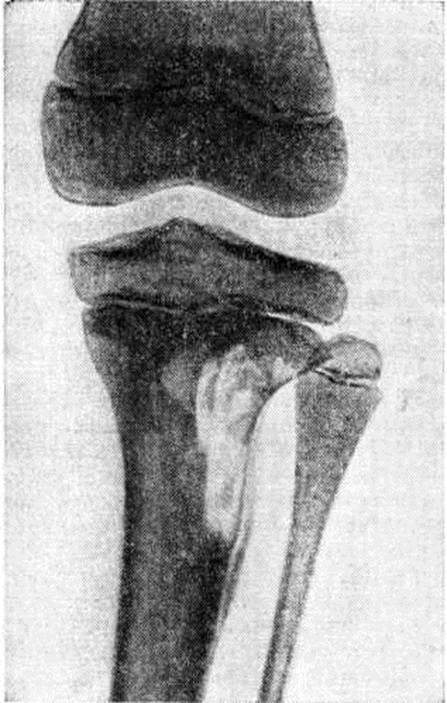

У взрослых рентгенологическое проявления несколько отличаются. Чаще поражаются длинные трубчатые кости, в которых развиваются обширные периостозы (смотри полный свод знаний: Рахит). Деструктивные процессы в костях конечностей (рисунок 3) могут быть причиной их патологический переломов. Изменения в лёгких характеризуются чаще двусторонними мелкоочаговыми тенями, а иногда и гиперплазией внутригрудных лимфатических, узлов.